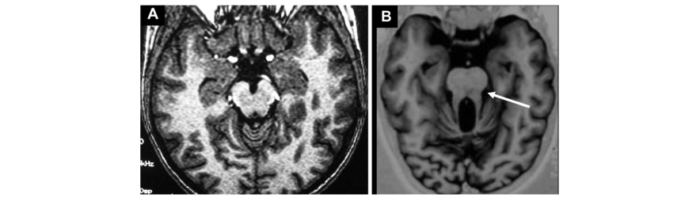

Sindrom Joubert este o afecțiune genetică rară, ce apare la un copil din 100.000 nașteri. Deși în majoritatea cazurilor apare la copii fără istoric familial de boală, în unele cazuri, boala poate fi moștenită.